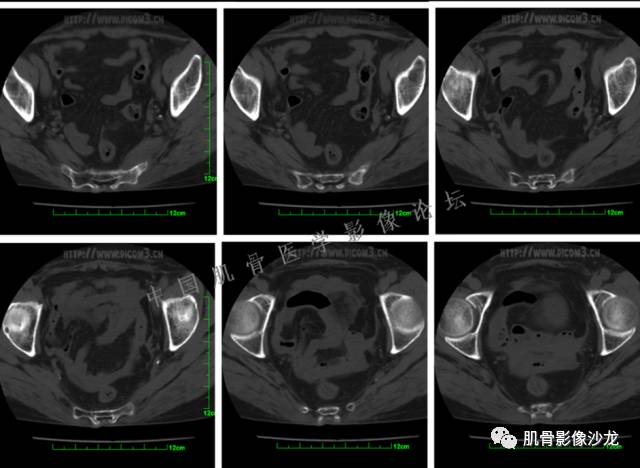

患者于2月前无明显诱因下出现腰骶部疼痛,夜间为重,逐渐加重伴左下肢麻木、疼痛,并有行走活动受限,在我院就诊,摄腰椎及骶髂部CT提示:腰椎骨质退变,腰3-4、4-5椎间盘膨出,骶髂关节炎。自用非甾体抗炎药无好转,再次来院就诊,门诊拟“骶髂关节炎”收住我科。病程无间歇性跛行,大小便正常。

专科检查:神清,脊柱无侧弯后凸畸形,椎体各节段无压、叩痛,双侧棘突旁无压痛,双侧骶髂关节压痛明显,左下肢放射痛,浅感觉较健侧减退,腰椎前屈后伸活动受限,膝、跟腱反射正常。

辅助检查:腰椎及骶髂部CT提示:腰椎骨质退变,腰3-4、4-5椎间盘膨出,骶髂关节炎。

雪舞 :第二例,位于骶骨,有骨质破坏并有软组织肿块,软组织肿块边界清

雪舞 :第二例挺难的,骨质破坏是溶骨性的,局部皮质中断,软组织肿块外缘光滑